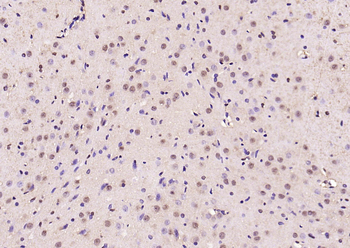

Phospho-Smad3 (Ser423 + Ser425) Rabbit Polyclonal Antibody [orb6983]

FC, IF, IHC-Fr, IHC-P, WB

Bovine, Canine, Equine, Gallus

Human, Mouse, Porcine, Rat

Rabbit

Polyclonal

Unconjugated

100 μl, 200 μl, 50 μlPhospho-SMAD5 (Ser463 + Ser465) Recombinant Rabbit Monoclonal Antibody [orb559123]